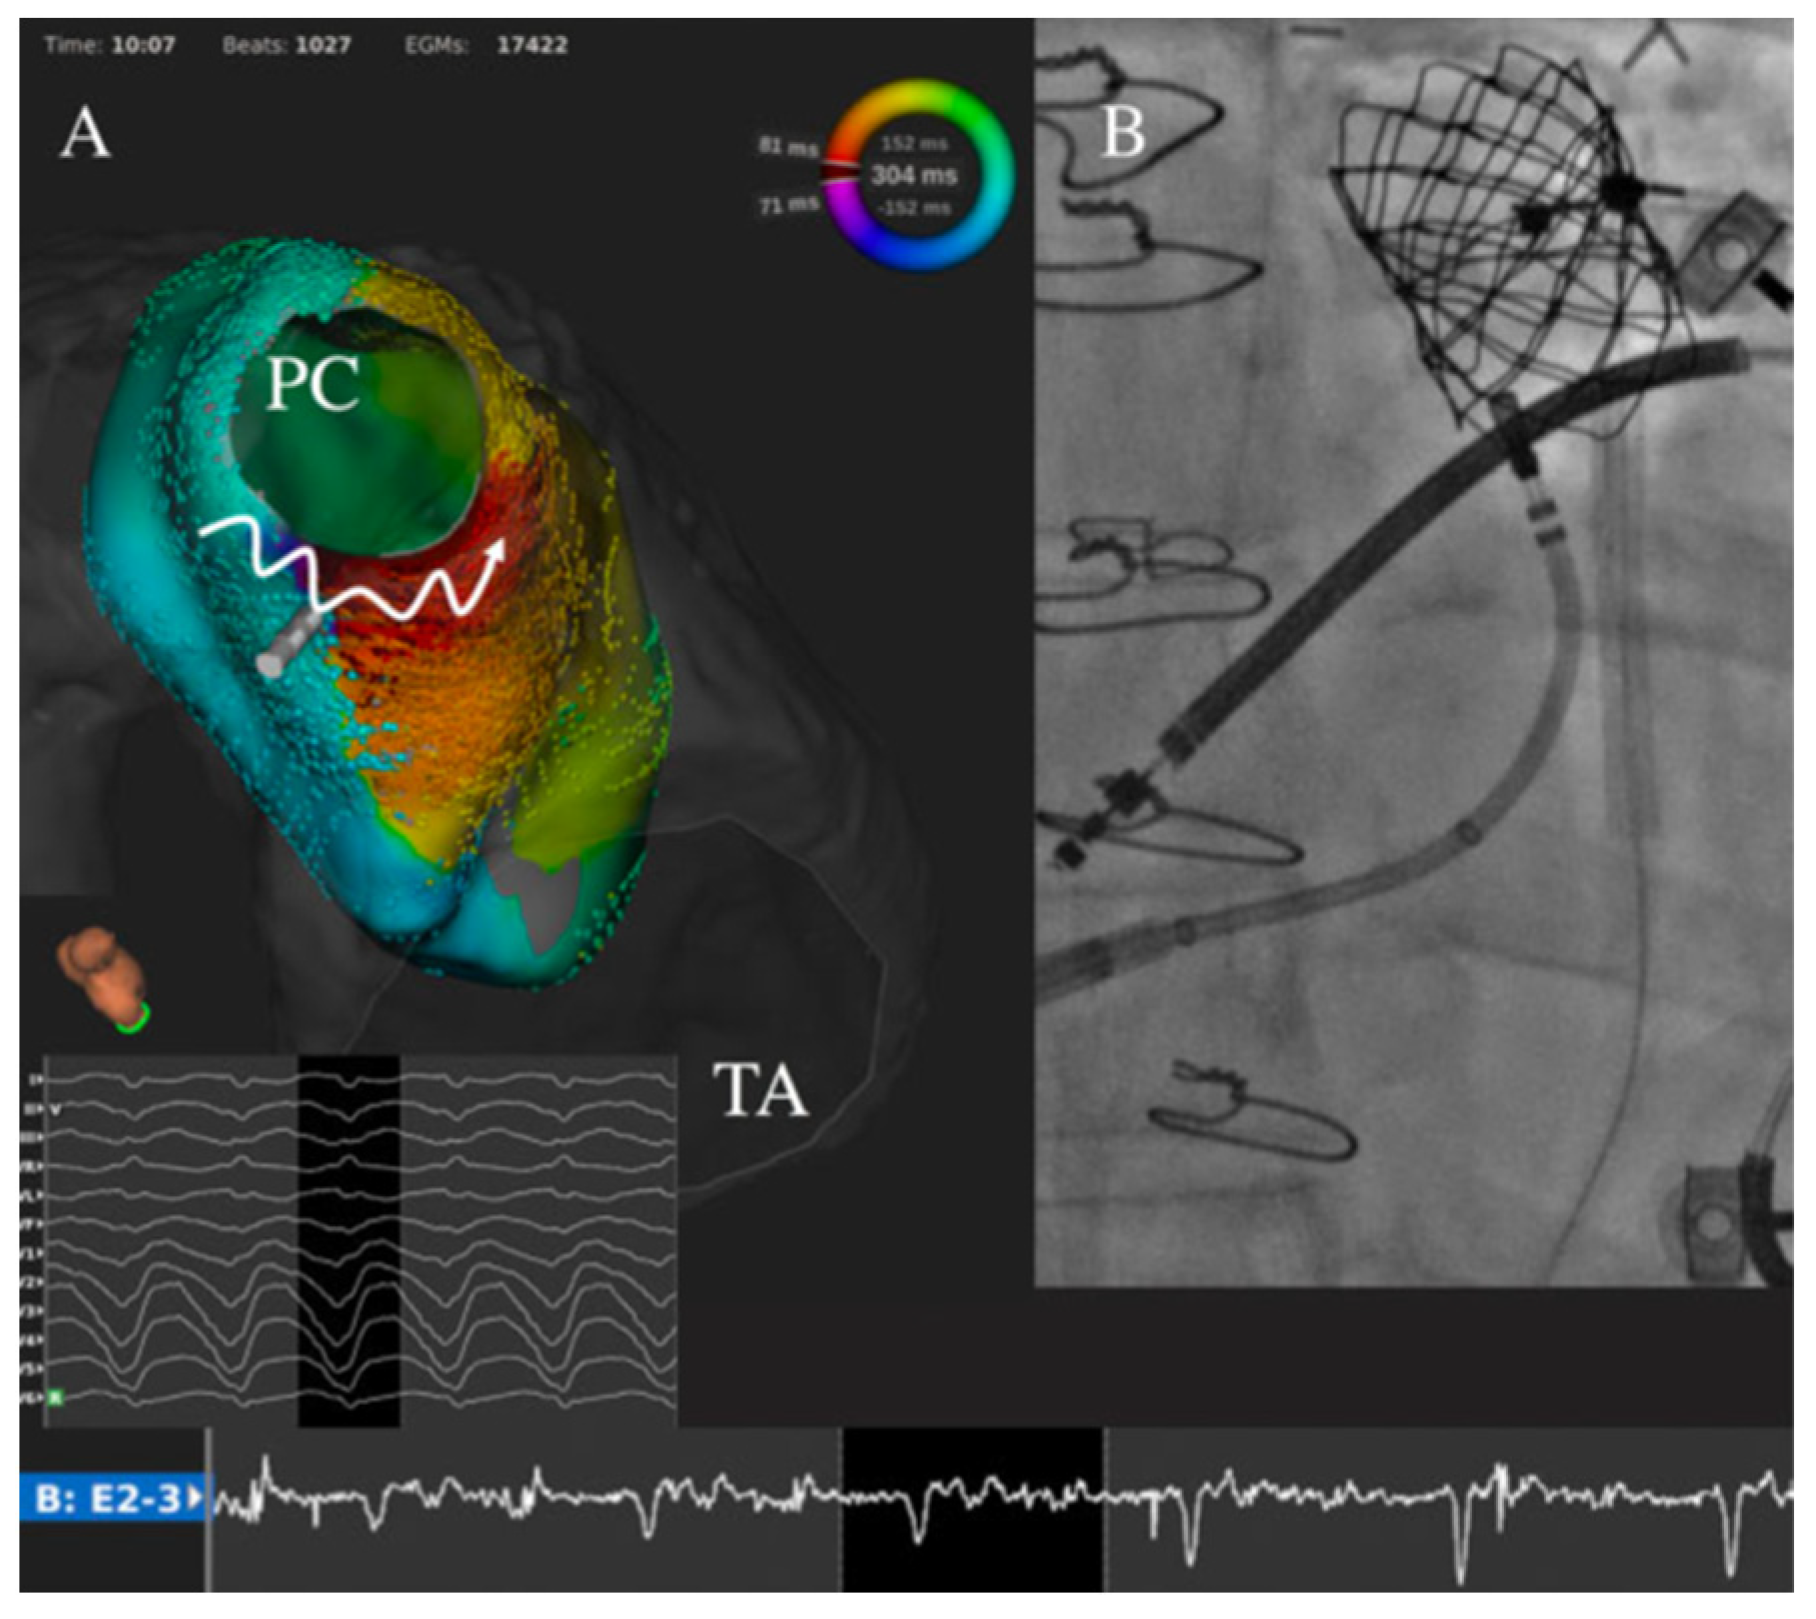

The advent of three-dimensional electroanatomic mapping systems and advances in ablative techniques have resulted in significant improvement in outcomes (Figure 2) [47,48]. Target sites for ablation are selected by combining voltage mapping, which localizes areas of scar tissue, activation mapping and pacing maneuvers to elucidate arrhythmia mechanisms and localize critical components of the arrhythmia substrate. The use of irrigated catheter tips has also been associated with more favorable acute outcomes. This may reflect the difficulties in creating transmural lesions in low-flow environments (which impair conductive cooling and limit power delivery of radiofrequency energy), as observed experimentally in certain types of surgical anatomies [49], as well as chronic volume and pressure loads that result in marked thickening of myocardial walls [50]. Image integration combining pre-procedural high-resolution computed tomography or magnetic resonance imaging with electroanatomic maps also facilitates a more thorough understanding of complex anatomical details. These imaging techniques may prove complementary information regarding structural substrates to target.

Figure 2.

Catheter ablation in congenital heart diseases, technological advances for challenging cases.

Figure 4.

Ventricular tachycardia catheter ablation in a patient with tetralogy of Fallot with transcatheter pulmonary valve. The clinical ventricular tachycardia (cycle length 301 ms, 198 bpm) was easily inducible. Very-high density mapping (Rhythmia system, Boston Scientific, USA) revealed that circuit rotated around the pulmonary valve with the critical isthmus identified between the right ventricle to pulmonary artery conduit and the ventricular septal defect patch (A). A linear ablation by irrigated radiofrequency (50 W) slowed and then terminated the arrhythmia. Despite complementary applications including with retrograde aortic approach, a complete bidirectional block was not achieved as the superior part of the isthmus was covered by the transcatheter pulmonary valve (B). Reproduced with permission from Combes et al. [60].